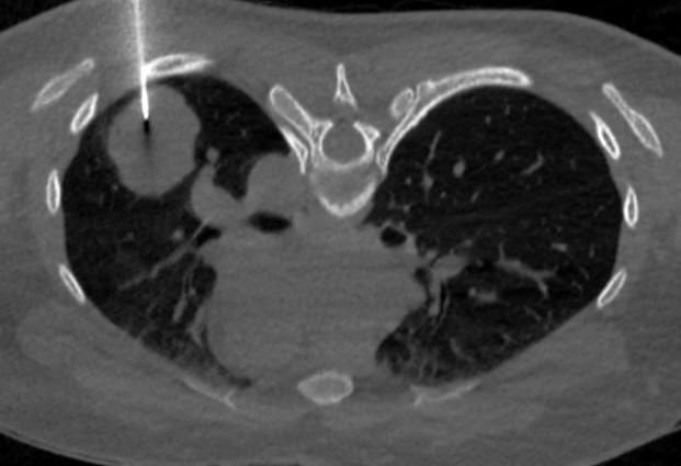

Qua thăm khám lâm sàng kết hợp máy soi da và sinh thiết, các bác sĩ xác định đây là ung thư tế bào hắc tố giai đoạn sớm. Do tổn thương chưa xâm lấn sâu và chưa di căn, bệnh nhân được phẫu thuật cắt bỏ triệt để khối u, không cần điều trị phức tạp khác. Sau phẫu thuật, kết quả theo dõi cho thấy chưa phát hiện di căn, sức khỏe bệnh nhân ổn định và sinh hoạt bình thường.